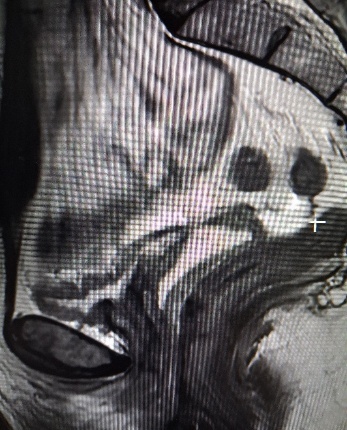

- Αξονική ή/και μαγνητική τομογραφία κάτω κοιλίας